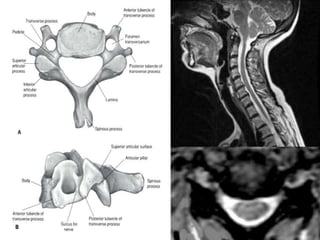

Note:the black line directly posterior to the vertebral bodies and relative

Thinning of spinal cord, note normal disc height

Note:the black linedirectly posterior to the vertebral bodies and relative Thinning of spinal cord, note normal disc height